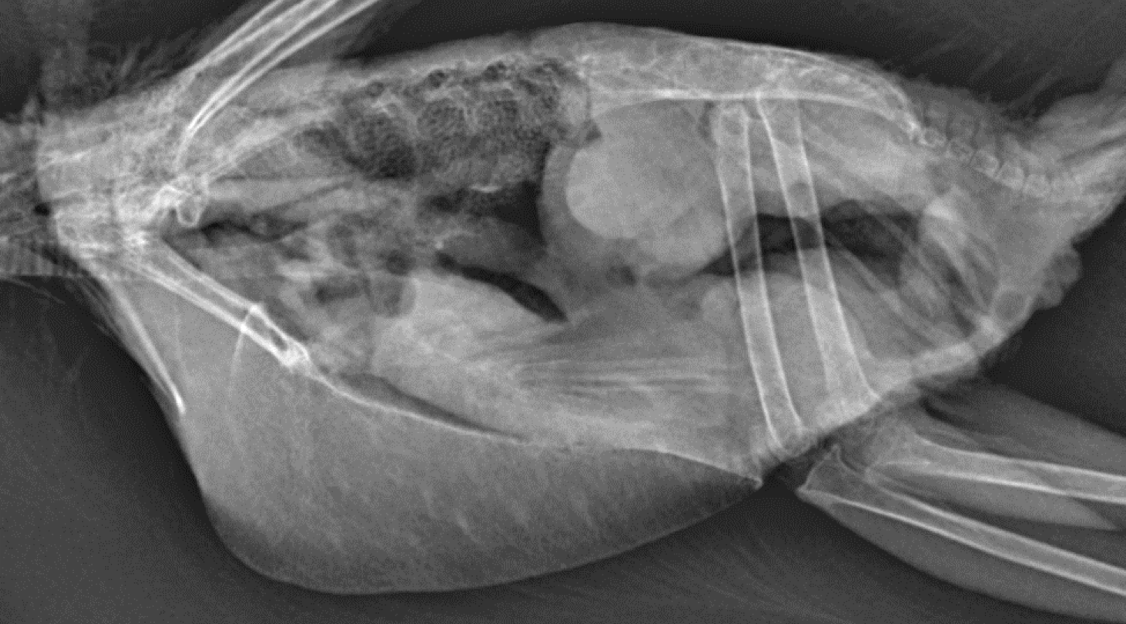

What is wrong?

Proventricular dilation

metal/grit in ventriculus